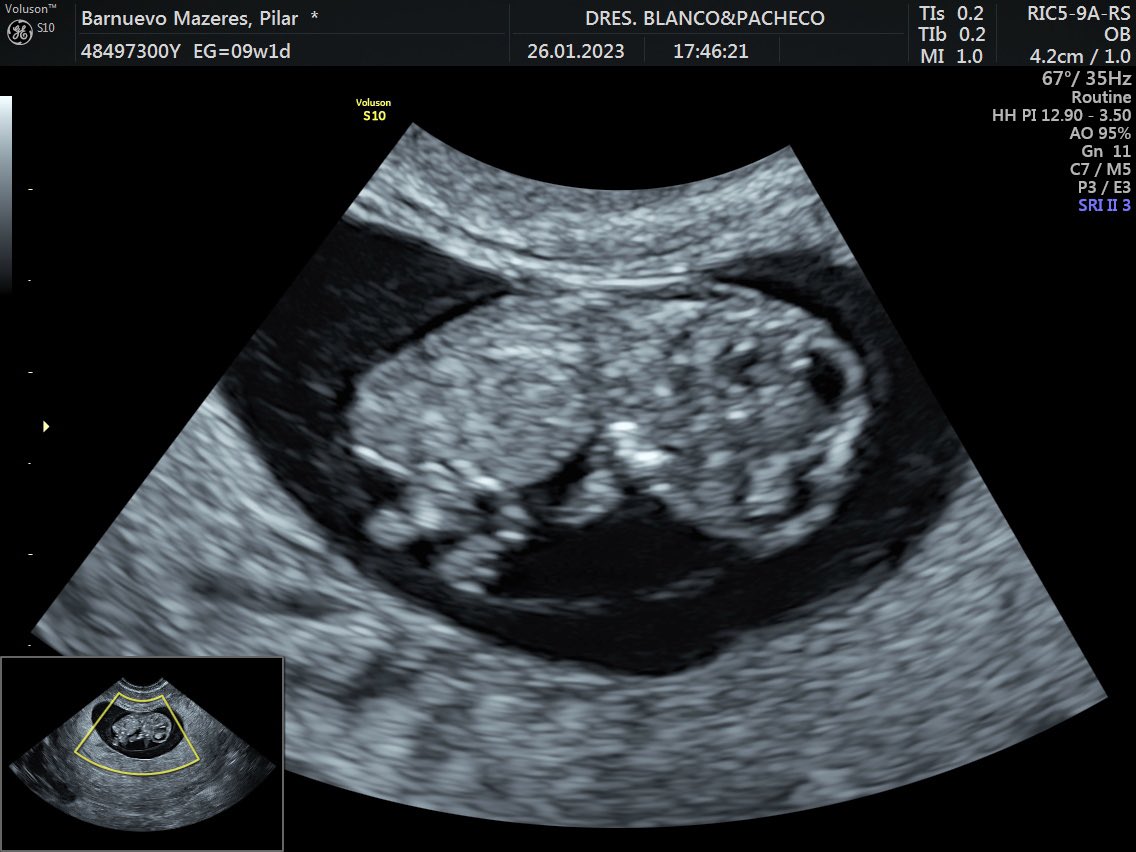

🇪🇸🇺🇸Como algunos ya sabéis, nos volvemos de USA. Dejamos un montón de buenos recuerdos en Boston y amigos en el MIT, pero es que hay otras experiencias más importantes en la vida que mejor hacerlas en España…#Vamosaser4👶🏻